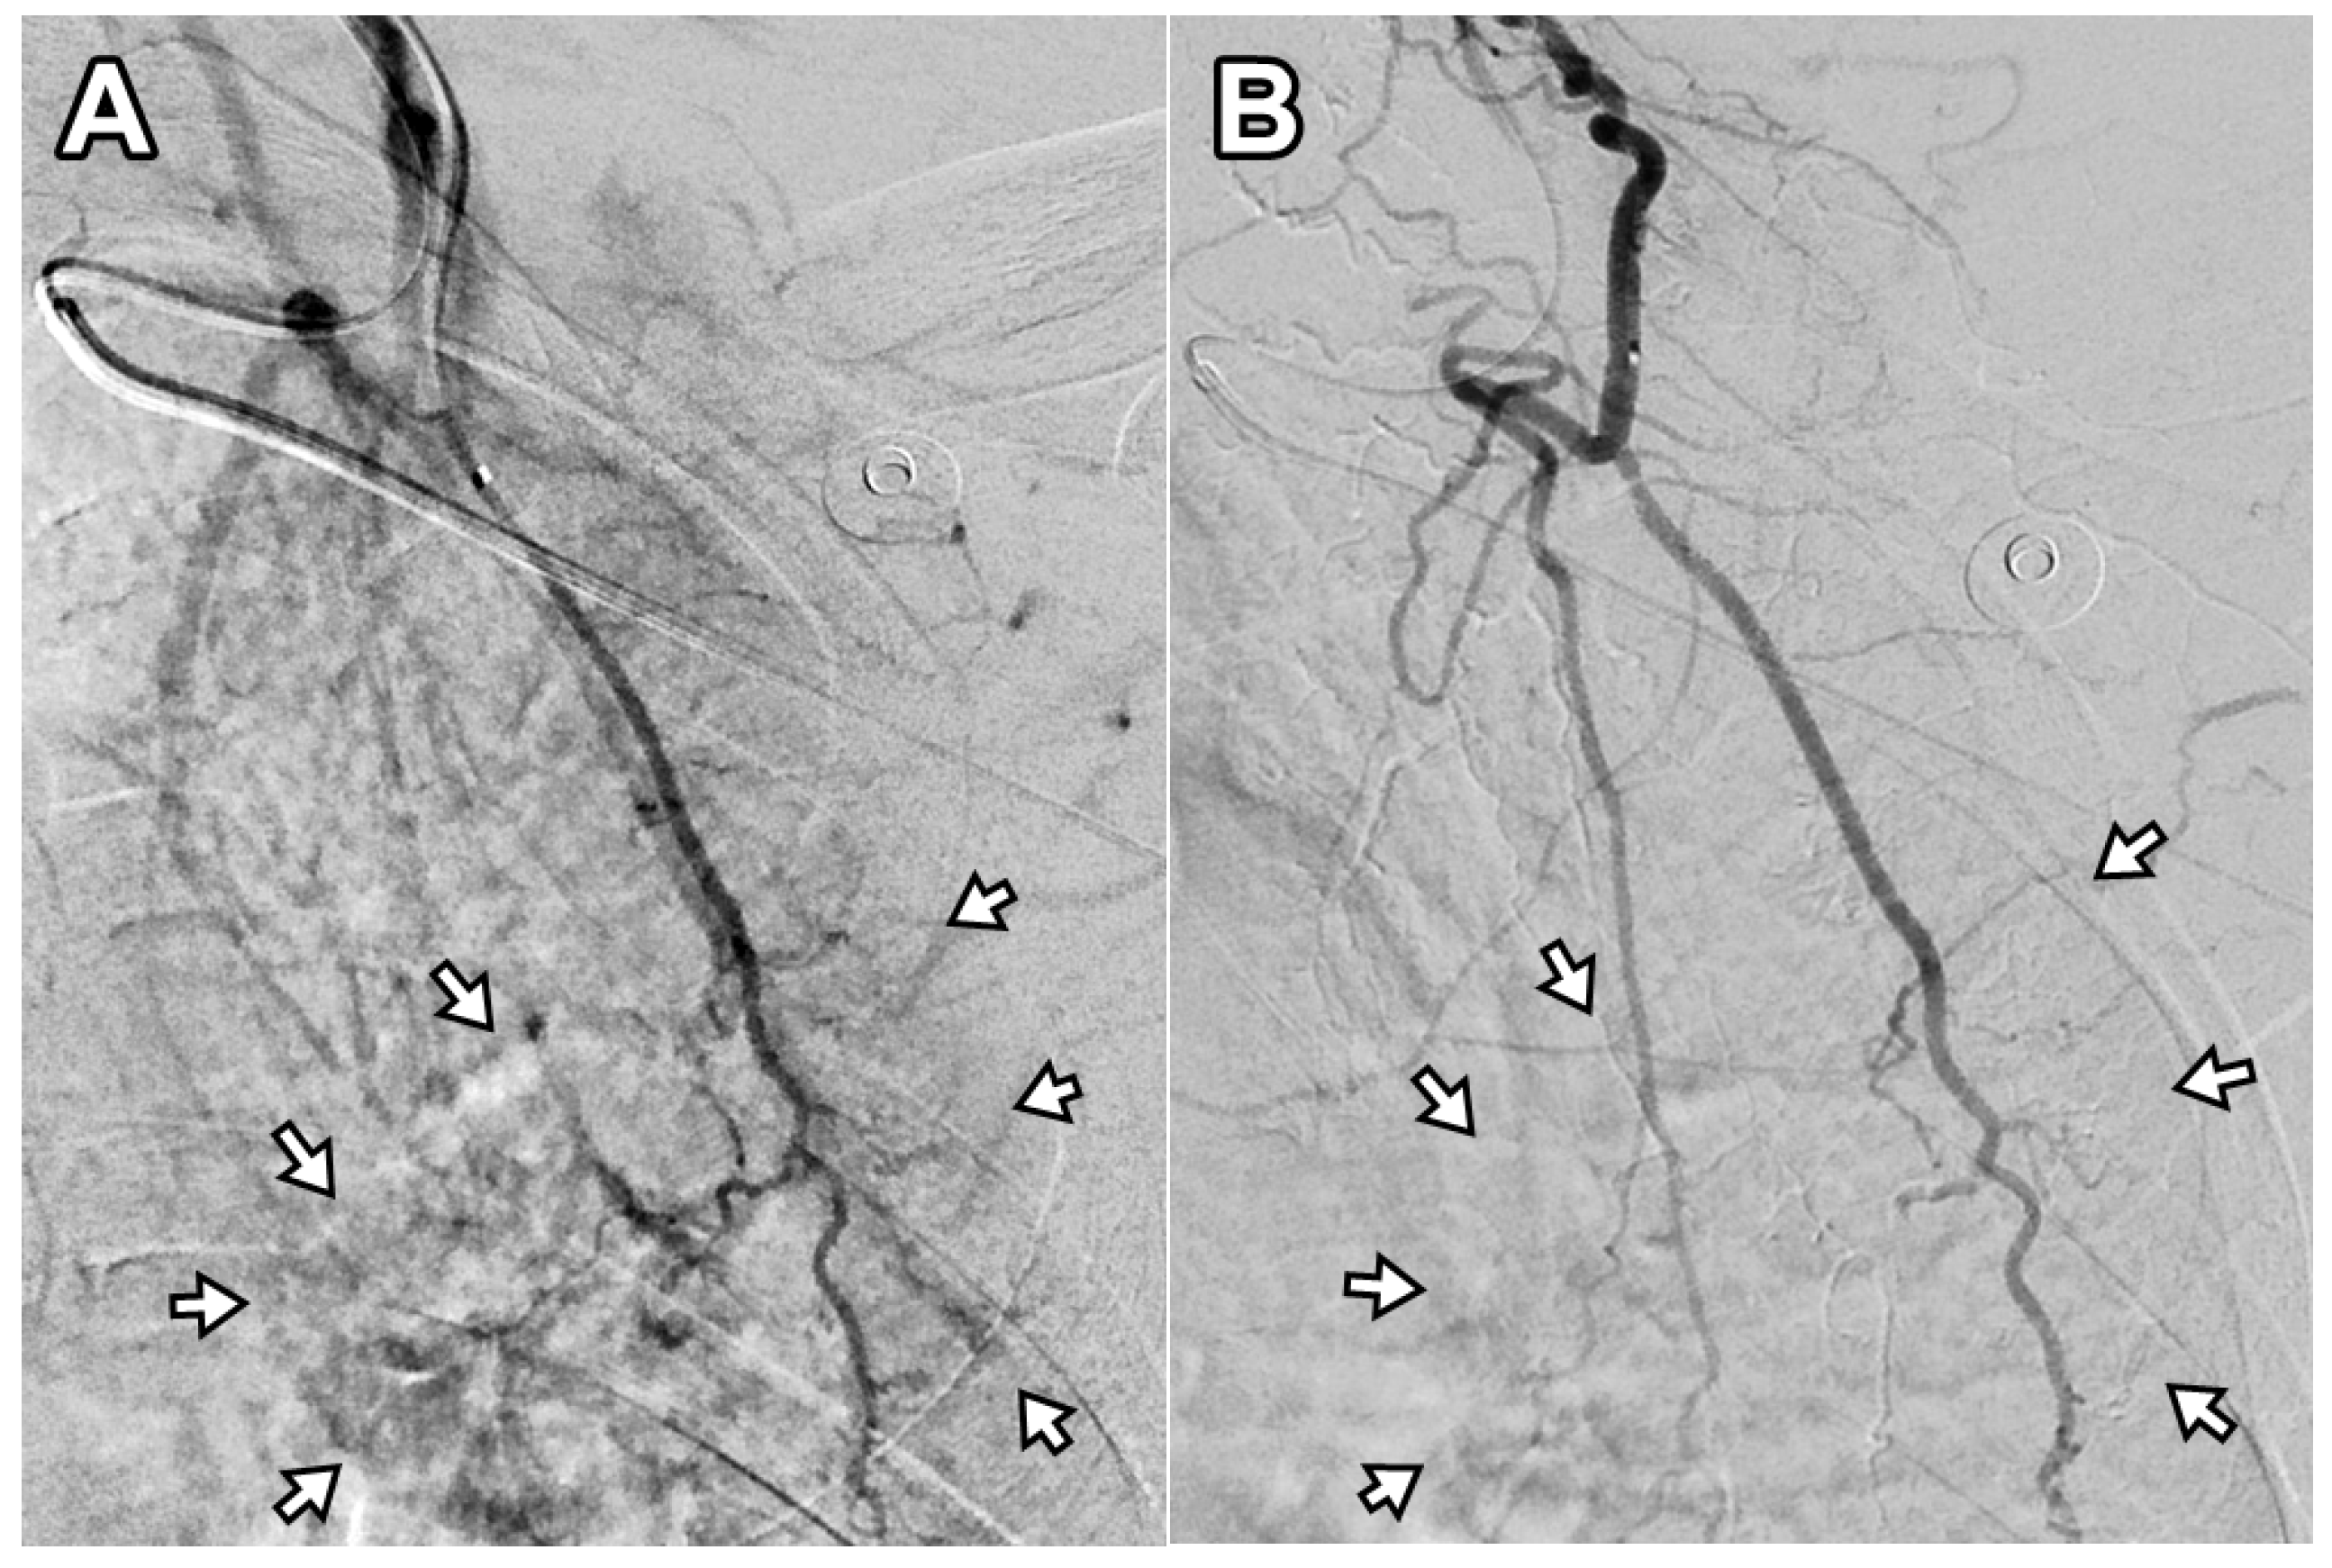

3.2. Pain Changes After TAE

Two patients required a second TAE procedure due to persistent pain at 75 and 41 days after the initial treatment. A total of 12 TAE procedures were performed in 10 patients, achieving a technical success rate of 100% (12/12). On average, 1.8 ± 0.9 arterial branches were embolized per procedure, and 171 ± 54.2 mg of IPM/CS was used per TAE. An illustrative case is presented in Figure 2. Following TAE, the NRS score significantly decreased to 2.1 ± 0.7 at 1 month, 2.0 ± 1.1 at 3 months, and 1.9 ± 1.2 at 6 months (p < 0.001). Clinical success, defined as an NRS reduction of ≥50% from baseline, was achieved in 90% (9/10), 100% (10/10), and 90% (9/10) of patients at 1, 3, and 6 months, respectively. The reduction in NRS score after TAE was significantly greater at 1 month, 3 months, and 6 months when compared with the last follow-up data of the injection-only group (p = 0.024, 0.005, and 0.006, respectively). The percentage of NRS score change was −70.2%, −73.4%, and −74.8% at 1, 3, and 6 months post-TAE, showing no significant difference compared with the last follow-up data of the injection-only group (−69.7%; p = 0.931, 0.486, and 0.397 at 1, 3, and 6 months post-TAE, respectively). The changes in NRS score over time are illustrated in Figure 3. A detailed comparison of pain score reductions and percentage changes between groups following injection and TAE is shown in Table 2. Detailed individual patient-level data, including baseline NRS, pain duration, type of injection, TAE details, and follow-up NRS, are provided in Table S1.

Figure 2. Digital subtraction angiography of the deep branch of the left transverse cervical artery in a 56-year-old woman with refractory interscapular pain. (A) Pre-embolization image shows abnormal neovascularization in the interscapular area (arrows). (B) Post-embolization image demonstrates disappearance of abnormal blush in the corresponding area (arrows). This patient experienced a decrease in NRS score from 6 to 2 at 6-month follow-up (67% reduction).